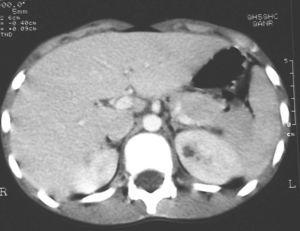

Paciente de 12 años que inicia con dolor cólico en región subcostal y flanco izquierdo; tras 24 h de evolución, presenta fiebre de 38 °C sin otra sintomatología. En la ecografía abdominal se objetiva una lesión hipoecogénica en tercio inferior de RI que correspondía a una NA (fig. 1). Se inicia tratamiento con cefotaxima. El paciente continúa febril, con persistencia del dolor y elevación de los reactantes de fase aguda, todos los urocultivos y hemocultivos son negativos. Se añade cloxacilina al cuarto día del ingreso, al objetivar una lesión cutánea en el maléolo interno izquierdo, con aspecto séptico, secundaria a una epidermólisis ampollosa de base. Se detecta al sexto día en la auscultación pulmonar crepitantes en la base izquierda. Pese a haberse realizado una radiografía que fue normal el día del ingreso, se realiza un control en el que se objetiva una condensación retrocardíaca izquierda. Se replantea el diagnóstico y se realiza una TC en el que se objetiva imagen compatible con nefronía de 2 cm en el polo inferior del RI y un absceso de 1 cm en el polo superior (fig. 2). Mantiene fiebre durante 7 días. Se sustituye la cefotaxima por ceftazidima con la que completa 10 días de tratamiento y se añade eritromicina durante 7 días y completa 21 días con cloxacilina oral. La ecografía se normaliza a los 26 días. La gammagrafía a los 6 meses de la infección descarta cicatrices renales.

Figura 2.TC abdominal con contraste intravenoso. Se observa un área hipocaptante de 1 cm de diámetro localizada en polo superior de riñón izquierdo, compatible con absceso.